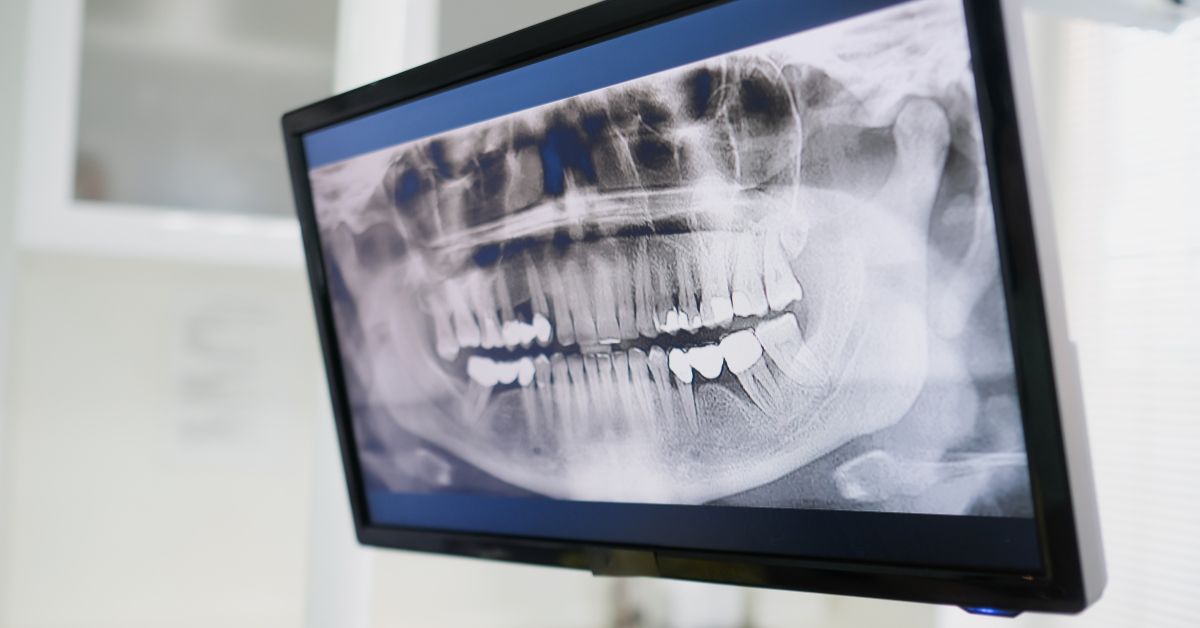

Panoramska snimka (ortopan)

Prikazuje sve zube, čeljusti i okolne strukture u jednoj slici. Koristi se kao osnovna dijagnostička snimka u većini slučajeva.